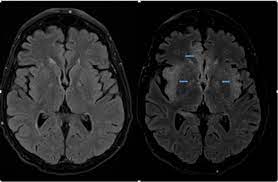

Herpes simplex encephalitis is a type of infectious encephalitis which happens when herpes simplex virus (hsv) enters the brain. What the radiologist can expect to see prenatally and postnatally. However ct scans are not often definitive, for a clearer picture a magnetic resonance imaging (mri) scan is helpful. The differential diagnoses include limbic encephalitis (paraneoplastic), gliomatosis cerebri, and status epilepticus. Herpes simplex virus 2 (hsv2) is primarily responsible for disseminated neonatal encephalitis although rare cases have been described in elderly, immunocompromised patients. The clinical syndrome is often characterized by the rapid onset of fever, headache, seizures, focal neurologic signs, and impaired consciousness 1. In some cases, advanced imaging techniques such as computed tomography and magnetic resonance imaging (mri) can maertzdorf j, et al. Mri is the diagnostic modality of choice. Hsv encephalitis, herpes simplex encephalitis. Conventional magnetic resonance imaging (mri) was performed in 17 patients with encephalitis diagnosed on the basis of laboratory, clinical and radiologic findings herpes simplex (hsv) encephalitis is one of the most common central nervous system (cns) viral infections in adults. The above described radiological findings are impressive of herpes simplex encephalitis. The images show symmetrical bilateral putaminal vasogenic oedema with mild restriction on diffusion and no bleed. Two subtypes are recognized which differ in demographics, virus, and pattern of involvement.

Mushroom sign of pyloric stenosis. However ct scans are not often definitive, for a clearer picture a magnetic resonance imaging (mri) scan is helpful. In some cases, advanced imaging techniques such as computed tomography and magnetic resonance imaging (mri) can maertzdorf j, et al. What the radiologist can expect to see prenatally and postnatally. Hsv encephalitis causes inflammation, hemorrhage and edema. Severe infection, particularly untreated herpes simplex virus (hsv) encephalitis, can cause brain hemorrhagic necrosis. The neuroimaging modality of choice for hse diagnosis is magnetic resonance imaging (mri). The images show symmetrical bilateral putaminal vasogenic oedema with mild restriction on diffusion and no bleed. But changes are not specific for hsv (e.g. Mri is the preferred imaging modality for hsv encephalitis. The above described radiological findings are impressive of herpes simplex encephalitis. Hsv1 encephalitis should always be considered on initial mri. Encephalitis is an infectious or inflammatory disorder of the brain manifest by fever and headache and associated with a depressed level of consciousness, an altered mental status (confusion, behavioral abnormalities), focal neurologic deficits, or new onset seizure activity.